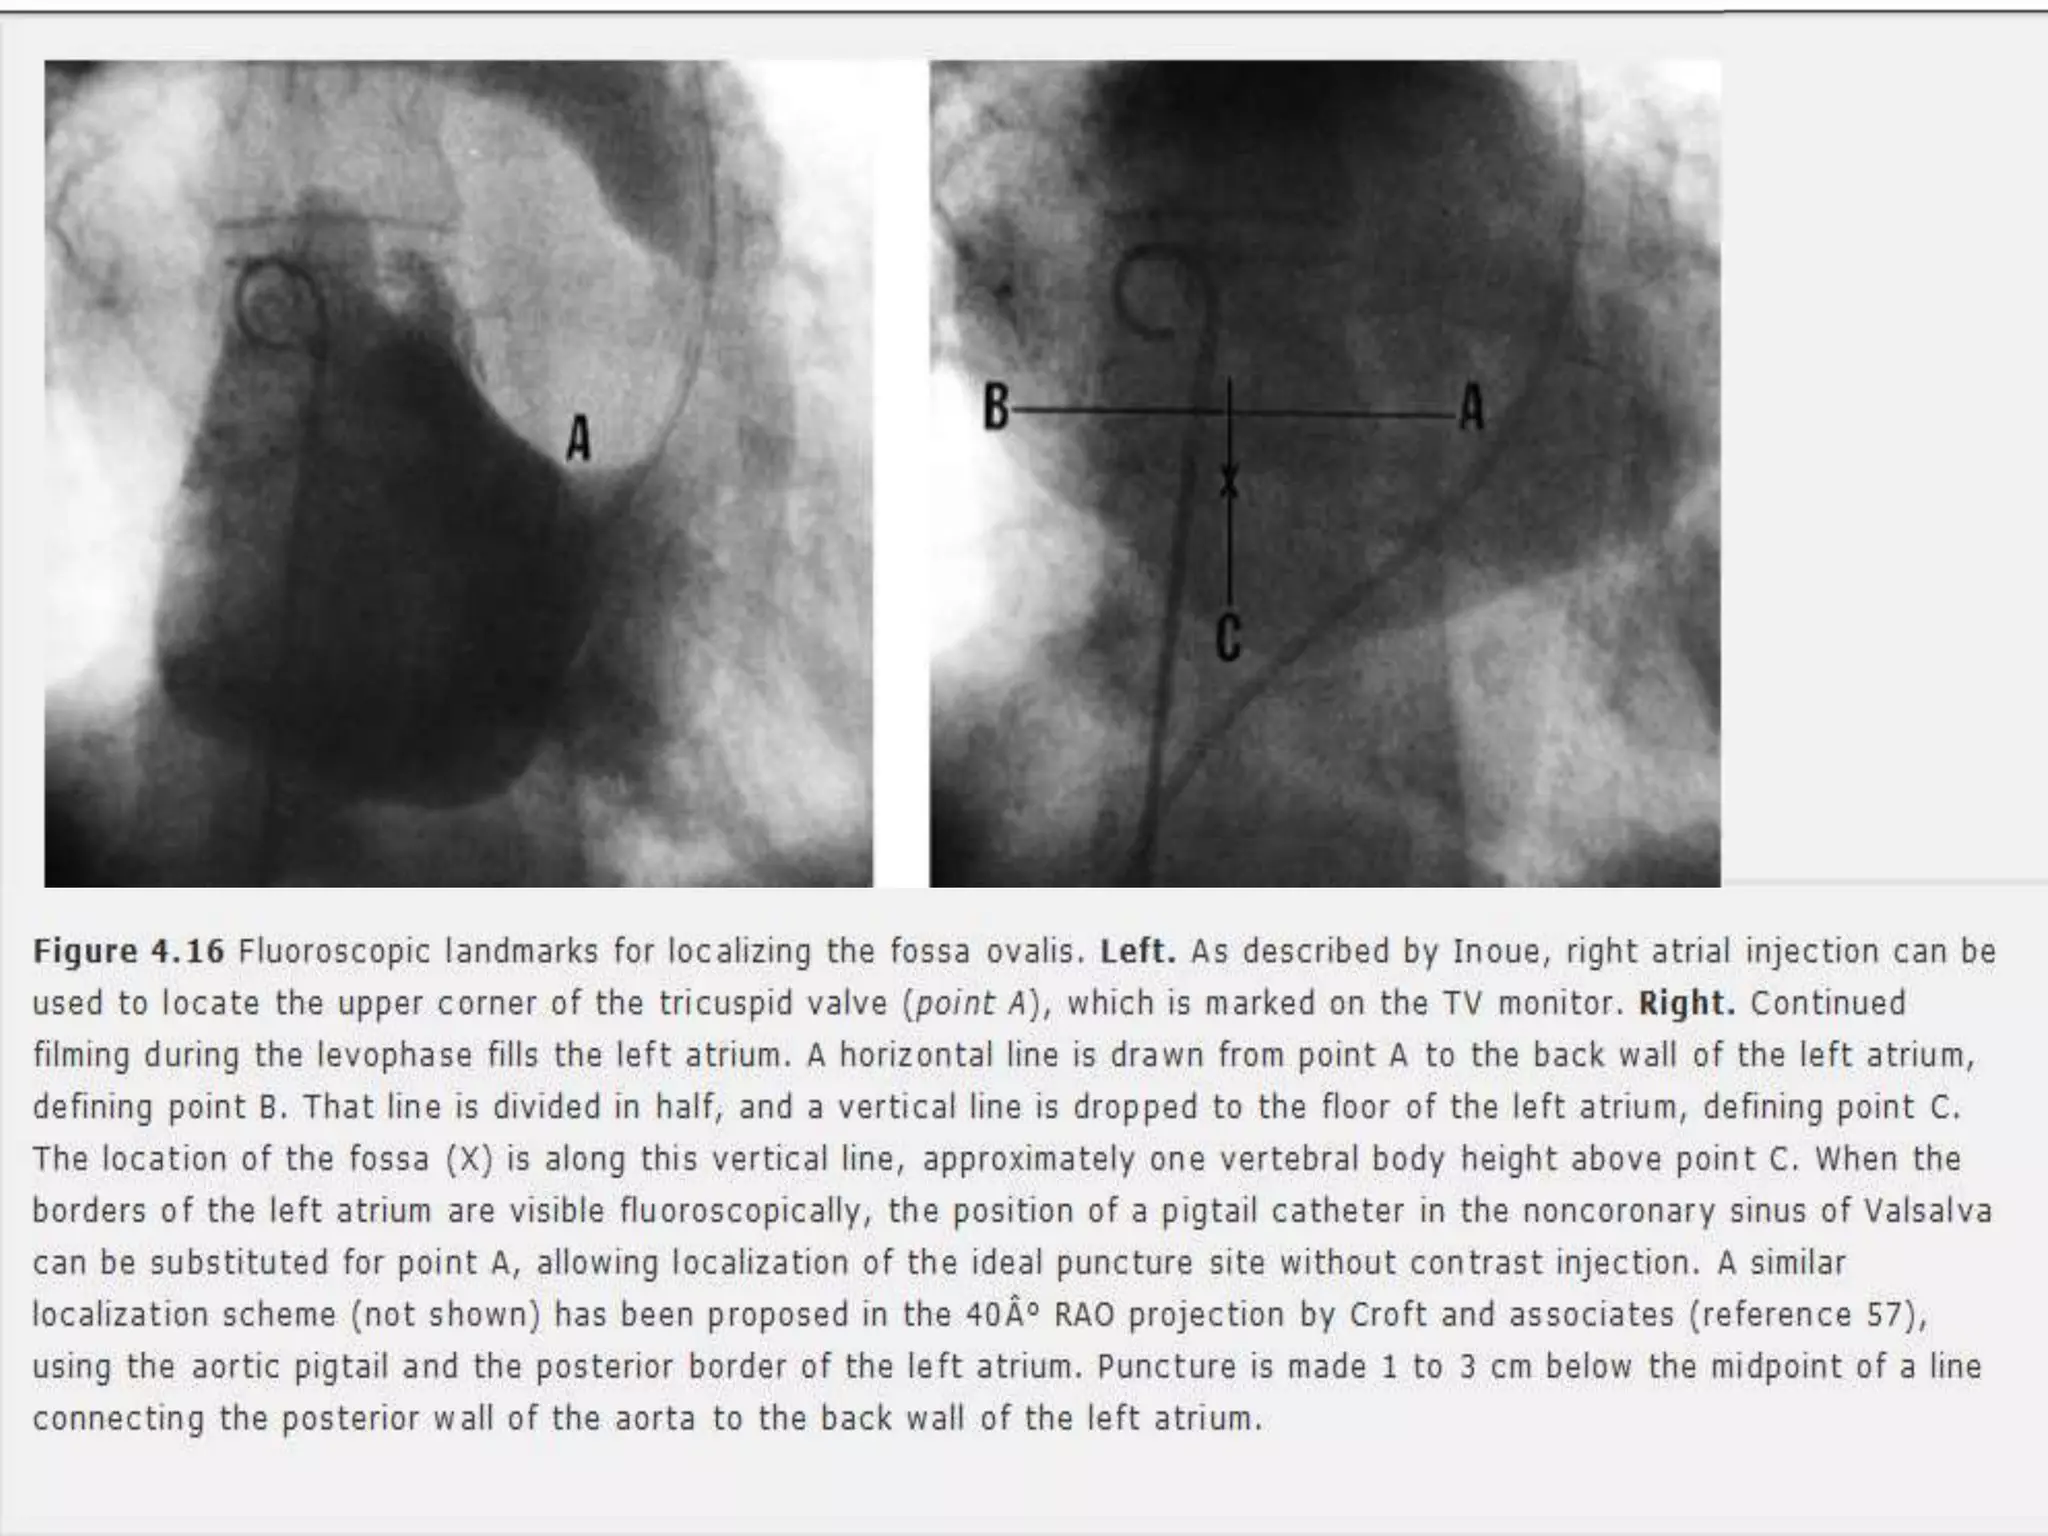

 PBMV,Access to pulmonary veins.

 Complication rate <1%.

 Procedure:

• 8F Mullins transseptal sheath and dilator

• Brockenbrough needle. 18 G -21G at tip.

• 0.032 inch guide wire – FV - RA – SVC.

• Mullins sheath and dilator advanced over the wire into SVC.

• Guidewire is removed and replaced by Brockenbrough needle.

• Catheter is rotated from 12 o’– 5 o’ clock position.

• Two abrupt right ward movements. – SVC to RA, Limbic edge of

fossa ovalis.

• Septal puncture done under fluoroscopy guidance.

• LA pressure recorded.

• LV angiography if needed – slight counterclockwise rotation.

 PBMV,Access topulmonary veins.  Complication rate <1%.  Procedure: • 8F Mullins transseptal sheath and dilator • Brockenbrough needle. 18 G -21G at tip. • 0.032 inch guide wire – FV - RA – SVC. • Mullins sheath and dilator advanced over the wire into SVC. • Guidewire is removed and replaced by Brockenbrough needle. • Catheter is rotated from 12 o’– 5 o’ clock position. • Two abrupt right ward movements. – SVC to RA, Limbic edge of fossa ovalis. • Septal puncture done under fluoroscopy guidance. • LA pressure recorded. • LV angiography if needed – slight counterclockwise rotation.